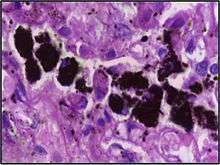

Alveolar macrophages are frequently seen to contain granules of exogenous material such as particulate carbon that they have picked up from respiratory surfaces. Such black granules may be especially common in smoker's lungs or long-term city dwellers.